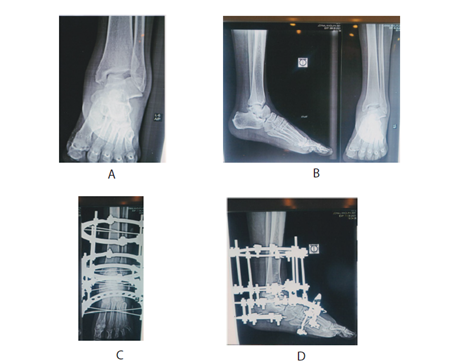

A and B show osteonecrosis of the talus after a talar neck fracture. C and D depict the situation after the application of the Ilizarov fixator.

From 1990 to 2023, we evaluated 64 patients with con rmed comminuted fractures or fracture-dislocations of the talar body, with a mean age of 27 years (range: 24-45), including 47 men and 17 women. In treating patients with fractures and fracture-dislocations of the neck of the talus, we prioritize e ective primary management and closely monitor for potential osteonecrosis, especially in displaced fractures. Early recognition is key; we typically evaluate patients with anteroposterior radiographs between 6 and 8 weeks post-injury to identify any signs of osteonecrosis. The Hawkins sign, indicated by a thin line of subchondral lucency, can suggest vascularity and help us rule out this diagnosis.3–5

When surgical intervention is necessary, we often excise the necrotic talus body and perform Blair type ankle fusion with Ilizarov, utilizing a sliding graft from the anterior tibia into the viable neck of the talus. We incorporate Ilizarov's technique alongside Blair fusion for enhanced stabilization and gradual correction of any deformities. To further improve anatomical integrity, we stabilize the calcaneus with an half ring. This technique ultimately leads to better outcomes for our patients.5,6